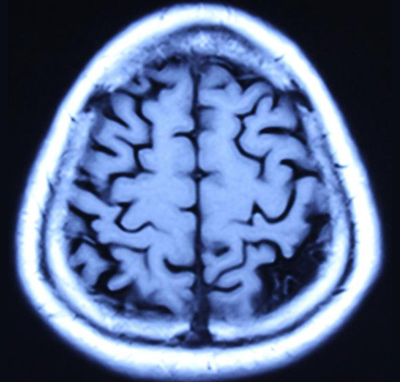

报告单1(治疗前) 报告单2(治疗后) 报告单1是孙先生治疗前, 2014年9月23日进行核磁共振(MRI)检查报告中检查所见:“幕下小脑、脑干亦萎缩明显”。报告单2是孙先生治疗后: 2014年11月29日用纯中药治疗2个月后,进行核磁共振(MRI)检查报告中检查所见:“幕下小脑未见异常信号”。临床症状明显消失。 典型病例二(影像比较):脑细胞再生长使脑组织增长 患者:周先生 男 76岁 退休干部,治疗前面无表情、意识不清,不能自己活动等。做核磁共振检查进行治疗前后比较如下:

图1-1 (治疗前) 图1-2(治疗前)

图1-3 (治疗后) 图1-4(治疗后) 上图是严重脑萎缩用中药治疗半年核磁共振影像的前后对比:周先生 男 76岁 面无表情,意识不清,记忆严重减退二年余,肢体活动困难,病情渐渐加重,对自己名字不知道,自己吃的什么饭不清楚,不能自己行走等病情,临床诊断为:阿尔茨海默病(老年痴呆症),脑中风后遗症。2018-年02月06日磁共振影像显示:脑萎缩(图1-1、图1-2下端黑洞脑组织严重缺损)。经中药治疗半年,患者面部病情正常,意识恢复正常,对自己的名字及他人都清楚,吃过的食物过后也记得,能够与他人正常交流,能够自己行走活动。2018年8月3日核磁共振影像(图1-3、图1-4)显示:脑萎缩与2018年2月6日(图1-1、图1-2)比较脑萎缩明显恢复(脑组织严重黑洞缺损消失)。影像证明了:经治疗使的脑细胞再增长,使脑组织增多,使脑组织逆生长。 我们编著了《大脑复原理论 大脑细微结构修复术》(成了脑科研究的参考资料)以及近期编著了《大脑复原理论 大脑医疗技术探秘》,介绍了脑细胞再生长的原理和临床治疗成功的验证,是我们中国人在国际上首先提出了脑细胞再生长和成功做到了脑细胞再生长!我们对大脑萎缩、小脑萎缩、脑科疑难疾病的有效治疗,是用核磁共振进行治疗前后的对比。 2016年6月在中国海南博鳌召开的“2016世界医疗旅游和世界健康学术大会”和2016年7月在曼谷召开的“世界传统医学大会”上,贾学铭教授发表并介绍用纯中药使脑细胞再生长治疗脑萎缩、阿尔茨海默(老年痴呆症)能够治愈的效果,用核磁共振影像片子进行治疗前后的对比,证明脑组织有了新的增多,做到了使脑细胞再生长的效果,改变了过去医学界不可治愈的理论,受到了美国、德国、澳大利亚、意大利、英国、法国等参会的代表和许多国家专家的认可和赞扬。这个“脑细胞能够再生长”的理论,到目前是贾学铭教授和贾沅潽医学博士首先提出的,也是首先用影像证明能够做到的,为人类健康事业流出一定的贡献。 在党的十八大以来,为强我中华,创新中医、发展中医,创新做到了用中医中药的方法,艰难的创新再创新的实践,做到了脑细胞再生长、脑组织能够再生长,造福了脑科疑难病患者,脑细胞再生长,治疗了大量的脑萎缩病人。对脑科医学理论和脑科疑难病治疗有重要的参考意义。在国际上产生了很好的影响,显示了中国中医药的魁宝,2016年7月在曼谷召开的世界传统医学大会上获得了《世界传统医学突出贡献奖》和《世界传统医学终身成就奖》。对现在及往后的脑科研究和脑科疑难病的治疗有重要的意义,为国际脑科医学的研究和治疗做出了显著的贡献。 贾学铭教授,贾沅潽博士介绍: 贾学铭,字:瀚珺,教授, 主任医师,从事中医工作50年,资深中医专家,中医脑科专家,中国传统医学名医,中国名人俱乐部副主席兼健康委员会主任,中华中医药学会专家委员,英国中医师学会知名专家、中医顾问,中国生命关怀协会心脑血管病防治指导专家,山东潍坊吉缘堂抗衰老中医药研究所法人等职。北京同仁堂中医医院贵宾楼专家,北京同仁堂王府井中医院心脑血管病专家,301医院远程医学中心专家,301健康管家心脑血管病专家,北京八大处中西医结合医院脑科专家。 贾沅潽医学博士,国外留学10年,2012年回国,山东潍坊吉缘堂抗衰老中医药研究所所长等职。通过我们研究治疗的临床案例等研究,2015年编著了《大脑复原理论 大脑细微结构修复术》,2019年编著了《大脑复原理论 大脑医疗技术探秘》,介绍了脑细胞再生长的原理和治疗的成功验证,是我们中国人在国际上首先提出了脑细胞再生长和成功做到了脑细胞再生长!为脑科医学作出了非常有意义的贡献! |